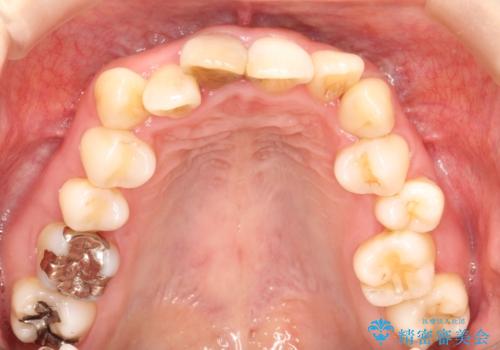

- 上下のがたつきを主訴に来院された患者様です。

上下の前歯と奥歯にがたつきがありました。

上下の奥歯を後方に移動させるのと、歯と歯の間をわずかに削ることでスペースを作り、歯を並べる計画としました。

インビザラインにて治療を行いました。